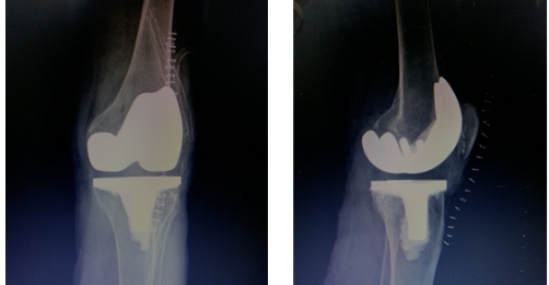

3月8日,哈尔滨医科大学附属第一医院群力院区骨科王文波教授团队应用术中便携式导航髓外定位截骨技术,成功为一名双侧严重弓形股骨的女性不开髓精准置换全膝关节,术后第二天患者便顺利下地行走。

经过术前详尽的规划预演,王文波团队在术中导航系统的辅助下,仅花费一个小时便顺利完成手术。术后患者感觉疼痛明显减轻,第二天便下地行走。

王文波介绍,IKPAS全膝关节手术定位系统利用传感器技术,术中实时测量计算获得个性化的角度数据,不开髓就可帮助医生术中精准截骨,定位假体安装位置,手术伤口小,有效降低并发症的发生,患者术后体验好,缩短术后康复时间。